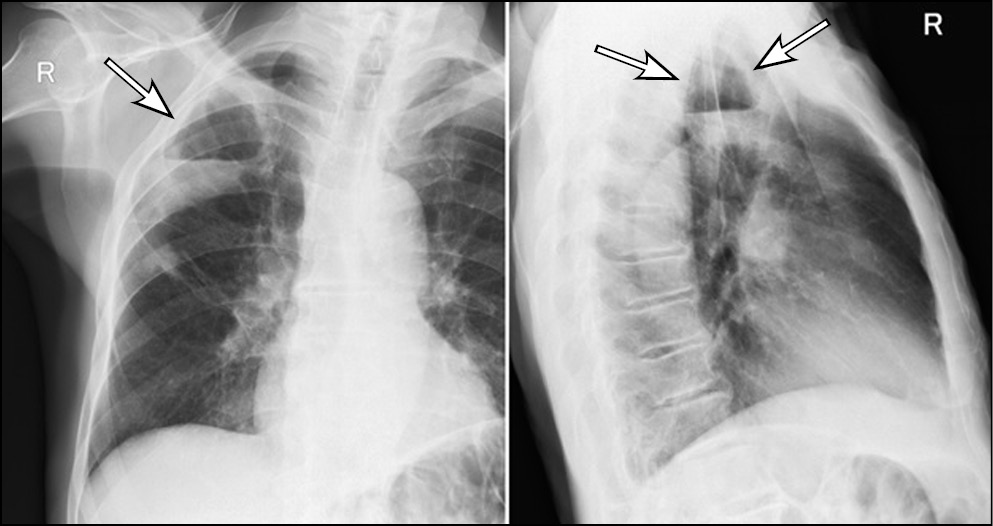

Диагностика острого абсцесса легкого по данным рентгенографии после его частичного опорожнения не представляет сложности: это кольцевидная тень с уровнем жидкости, контуры «кольца», обычно достаточно четкие (рис. 6). При рентгеноскопии или повороте тела можно наблюдать и изменение уровня жидкости в абсцессе (рис. 7). Сложнее с диагностикой абсцесса при его формировании, когда затенение не имеет типичных черт и может быть неправильной формы: оно представлено чаще круглой тенью или отграниченным затенением, центральные отделы которого могут быть несколько неоднородными, однако этот признак очень непостоянный.

Рис. 6. Рентгенография органов грудной клетки в прямой и правой боковой проекциях. Острый абсцесс в верхней доле правого легкого. В верхней доле справа имеется кольцевидная тень с небольшим горизонтальным уровнем жидкости, что свидетельствует о почти полном дренаже абсцесса. В S3 рядом с полостью — неоднородное затенение и сгущение легочного рисунка. [Изображения из архива авторов]. / Fig. 6. Chest X-ray. Acute abscess in the upper lobe of the right lung. In the upper lobe on the right there is a ring-shaped shadow with a small horizontal level of fluid, which indicates almost complete drainage of the abscess. In S3, next to the cavity, there is a non — uniform shading and thickening of the pulmonary pattern. [Images from the authors’ archive].

Рис. 7. Рентгенография органов грудной клетки в прямой и правой боковой проекциях. Острый абсцесс в верхней доле правого легкого. Полость в верхней доле справа на 1/3 заполнена жидкостью с горизонтальным уровнем, который соответствует положению пациента во время снимка (стрелки). [Изображения из архива авторов]. / Fig. 7. Chest X-ray. Acute abscess in the upper lobe of the right lung. The cavity in the upper lobe on the right is filled with liquid by 1/3 with a horizontal level that corresponds to the position of the patient during the image acquisition (arrows). [Images from the authors’ archive].